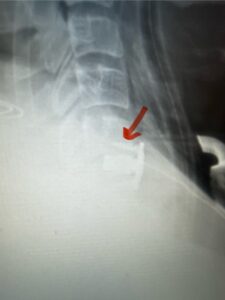

This 62 year-old female who had a prior ACDF from C3-C7 by an outside surgeon in 2009 and subsequent C5-C7 posterior cervical decompression and fusion in 2015 by our team, presents with progressive numbness, pain, and weakness of her arms. Above her prior anterior fusion, she had next segment degeneration with spinal stenosis resulting in spinal cord compression at C2-3 (Fig. 1).

Patient had an existing peripheral occipital nerve stimulator and therefore we had ordered a myelogram since it was not MRI compatible. The patient underwent a decompressive laminectomy and in situ fusion at C2-3. Care was made to preserve a good portion of the C2-3 facets bilaterally. It was felt that her C2 pars anatomically were not favorable to accept pars screws given the proximity of the vertebral foramen with a resultant narrow par (Fig. 2). She also had a normal C2-3 vertebral alignment. Post-operatively she had improvement of her arm pain and strength in right arm. In this case we made a decision to decompress the patient posteriorly given her prior anterior surgery, a more difficult approach to C23 disc space, and significant C23 disc collapse. A posterior approach was favorable in our opinion given the prior posterior surgery was more inferior with less scarring likely to be encountered in the C1-3 region. A posterior decompression also can yield a more adequate spinal cord decompression. Since we elected not to place pars screws because of her anatomy, and perform an in-situ fusion, careful attention was made to preserve as much of the C23 facet complex as possible.

Fig 1: Sagittal cervical CT myelogram demonstrating spinal cord compression at C2-3 above the prior anterior cervical fusion (red arrow)

Fig 2: Sagittal cervical CT pyelogram demonstrating a very narrow C 2 pars and prominent vertebral foramen making in unsafe to place a pars screw